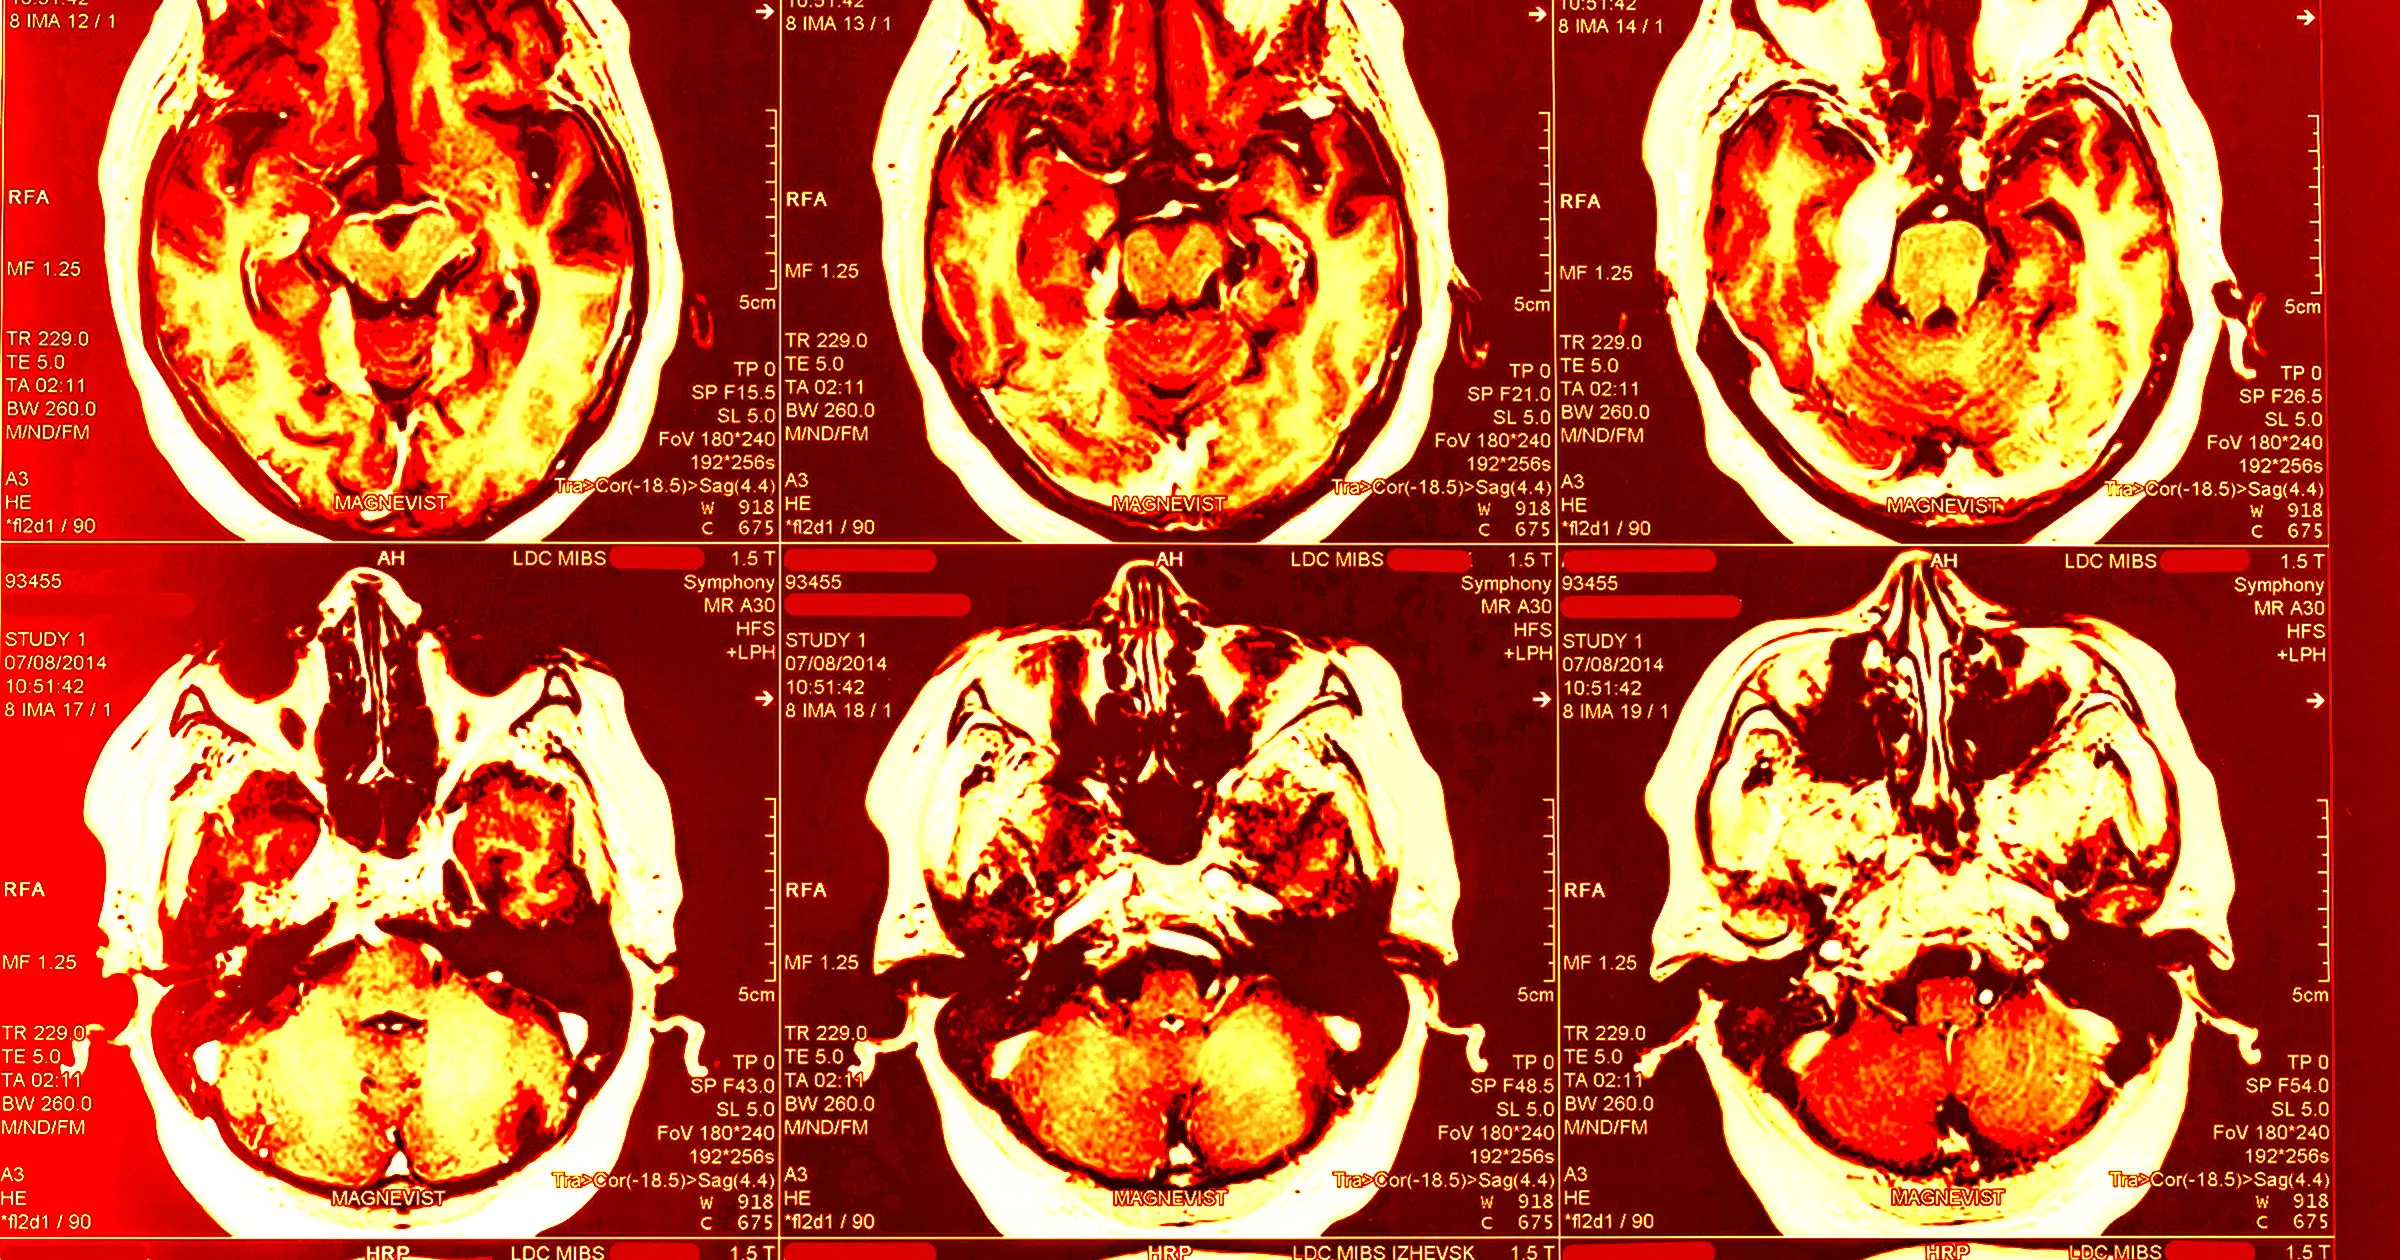

A medical examiner has found that former high school football player Shane Tamura — who shot and killed four people before taking his own life in the Manhattan building that houses the NFL headquarters in July — had chronic traumatic encephalopathy (CTE). CTE is a degenerative brain disease that has repeatedly been found in the brains of American football players, alongside athletes from other contact sports and soldiers. The grim findings about Tamura’s brain highlight how prevalent the disease has become among football players. A 2023 study by researchers at the Boston University CTE Center found that 345 of 376 deceased former National Football League players had CTE. Symptoms include depression, cognitive impairment, and suicidal thoughts. According to a statement quoted by the New York Times, the examiner “found unambiguous diagnostic evidence” of CTE in Tamura’s brain tissue. “The findings correspond with the classification of low-stage CTE, according to current consensus criteria,” the statement reads. After taking his own life, the 27-year-old Tamura left behind a note that expressed anger at the National Football League. The former player accused the NFL of hiding the effects of CTE in favor of profits. He also asked for his brain to be studied and therefore chose to shoot himself in the chest, not the head. Confusingly, Tamura appears to have targeted the wrong office in the building, though he did injure one NFL employee. In a statement to the NYT, the NFL carefully sidestepped any culpability. “There is no justification for the horrific and senseless acts that took place,” the sports league wrote. “As the medical examiner notes, ‘the science around this condition continues to evolve, and the physical and mental manifestations of CTE remain under study.'” In a study published last year, researchers found that one-third of former professional football players reported that they believe they have CTE. However, since diagnosis requires an autopsy, it’s difficult to determine whether their symptoms were the result of CTE or other causes. CTE arises from blows to the head and affects the region of the brain responsible for cognition and executive function. It can also affect the amygdala, which is associated with emotional control. “There is damage to the frontal lobes, which can damage decision making and judgment,” Boston University CTE Center director Ann McKee told the NYT in July following the shooting. “It can also cause impulsivity and rage behaviors, so it’s possible that there’s some connection between brain injury and these behaviors.” Tamura isn’t the first football player to perpetrate a mass shooting. In 2021, former NFL player Rock Hill killed six people before turning his gun on himself. Examiners later found that he had an “unusually severe” form of CTE. More on CTE: One Out of Three Former NFL Players Think They Have CTE, the Traumatic Brain Disease Linked to Murders and Suicides